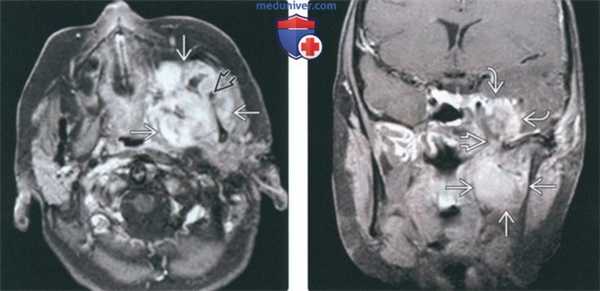

(Слева) При МРТ Т1ВИ в аксиальной проекции определяется объемное образование с сигналом промежуточной интенсивности, которое деформирует жевательное пространство и смещает кпереди заднюю стенку левой верхнечелюстной пазухи. Во всех последовательностях видны небольшие участки низкой интенсивности сигнала, которые представляют собой кальцификаты.

(Справа) МРТ Т2ВИ в аксиальной проекции, этот же пациент. Новообразование имеет гиперинтенсивный сигнал, характерный для опухолей хрящевой ткани. (Слева) МРТ Т1ВИ с КУ, аксиальная проекция, этот же пациент. Образование имеет неоднородную структуру и интенсивно накапливает гадолиний.

(Справа) КТ с КУ в аксиальной проекции, костное окно, этот же пациент. Определяется крупное новообразование, в толще которого «рассеяны» кальцификаты, образующие кольца и арки. Это типичные хрящевые кальцификаты. Наличие кальцификатов обычно говорит о низкой степени злокачественности опухоли.